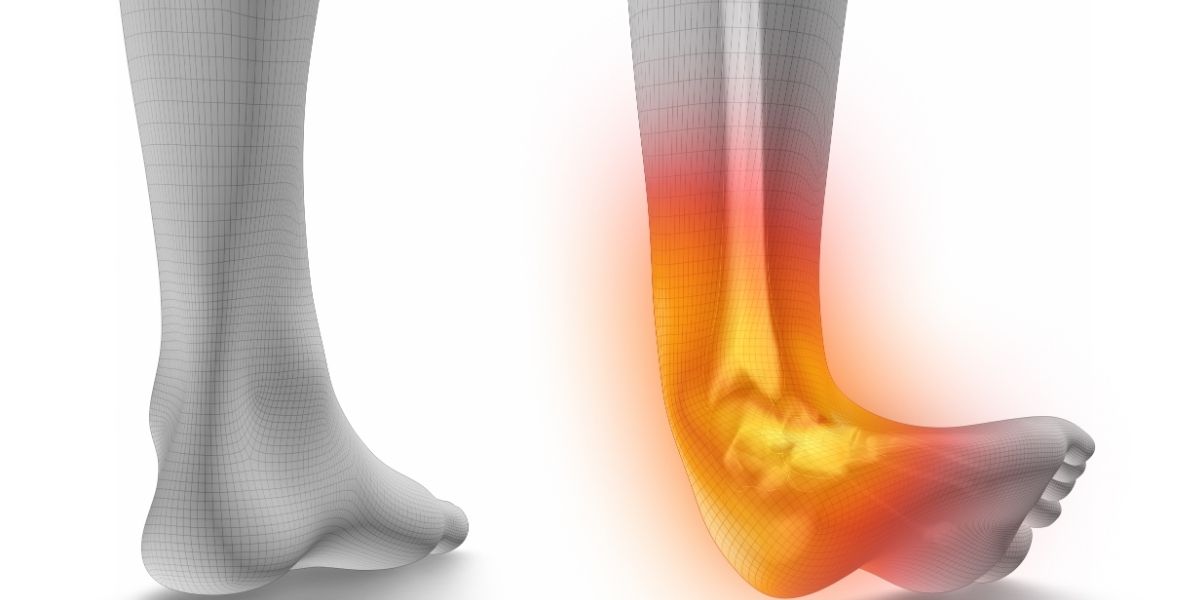

The human body relies on ligaments to connect bones and maintain the structural integrity of joints. In the ankle, these strong, fibrous tissues keep the bones in proper alignment during movements like walking, running, and standing. A sprain happens when these tissues stretch beyond their normal limits and cause damage to the fibers.

Medical providers classify the damage of an ankle sprain into three grades. Grade 1 involves minor stretching and microscopic tearing, leading to mild tenderness. A grade 2 sprain means the ligament is partially torn, which causes moderate swelling and some joint instability. Grade 3 is a complete tear of the ligament, leading to significant bruising, severe pain with weight-bearing, and noticeable instability. Most of these events involve an inversion injury, meaning the foot rolls inward and damages the lateral ligaments on the outside of the ankle.

Ankle sprains happen when the foot twists, rolls, or turns beyond its normal range of motion. Many individuals sustain this injury during athletic pursuits, as sports that require sudden stops, jumping, or sharp changes in direction place significant stress on the lower extremities. Everyday situations also present risks. Walking on an uneven sidewalk, stepping in a hidden hole in the grass, or slipping on a staircase may force the joint to roll awkwardly. Wearing footwear that lacks adequate support can also contribute to instability. When the twisting force is particularly strong, individuals might hear a popping sound as the injury occurs.